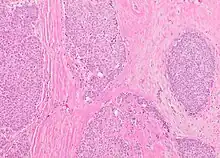

The microscopic histopathology (refer to adjacent high-power photomicrograph) of EPC tissues typically shows papillary structures with fibrovascular cores and proliferating neoplastic epithelial cells growing within cystic spaces, all of which are enclosed within a dense fibrous capsule. In general, EPC tumors do not have areas of neuroendocrine degeneration or myoepithelial cells.[6] The presence of a dense fibrous capsule distinguishes EPC from other papillary breast tumors, particularly PDCIS;[3] the absence of neuroendocrine differentiation areas helps distinguishes EPC from SPC tumors;[3] and the absence of peripherally located myoepithelial cells helps distinguish EPC from PDCIS tumors.[7] EPC tumors may be totally contained within their fibrous capsules or have one or more areas that have invaded through the capsule to normal breast tissues and/or chest muscles; these two variants are termed in situ EPC and infiltrative EPC, respectively.[3][5] In a study of 25 individuals with EPC, 14 had in situ and 11 had invasive disease with 6 of the invasive tumors rated as high grade (see high grade tumors) based on their microscopic histopathology.[5] Rarely, EPC tumors metastasize to nearby sentinel lymph nodes, other nearby axillary lymph nodes, and/or distant tissues; these metastases have in general shown papillary morphologic features similar to their primary tumors.[6] Uncommonly, EPC tumors co-exists with nearby PDCIS,[7] invasive carcinoma of no special type, invasive cribriform carcinoma of the breast, mucinous carcinoma, or tubular carcinoma[3] tumors.